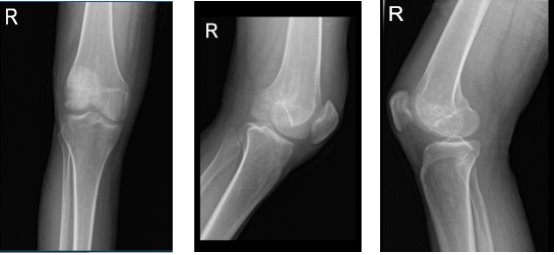

A drill hole was created about 2.5 cm proximal and anterior to the inferior and posterior articular surfaces of the femoral condyle under fluoroscopy guidance. It was inserted around 15 mm too.

Another drill hole was created in the lateral femoral condyle with a similar cannula around 0.5 cm proximal and anterior to the previous cannula. Pictures were obtained in the AP and lateral views and were deemed to be good.

Tricalcium phosphate bone cement was prepared and injected around 2.5 milliliters into each cannula. C-arm images revealed that the cement was only in the bone.

Right knee X-ray AP lateral and oblique 3 views